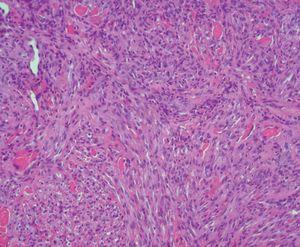

Figura 2. Panorámica de lesión tumoral que ocupa la dermis (hematoxilina-eosina original x100).

Figura 3. Proliferación fusocelular con formación de pseudocanales vasculares con abundantes hematíes (hematoxilina-eosina original x200).

Presentamos a un varón de 82 años remitido a nuestro servicio para la valoración de lesiones cutáneas en la región facial de crecimiento lento y curso asintomático de aproximadamente tres meses de evolución. Entre sus antecedentes destacaba una arteritis de la temporal, motivo por el cual se había prescrito tratamiento por vía oral con prednisona a dosis de 20-30 mg/día durante los últimos trece meses. En la exploración física se observaban cuatro o cinco lesiones tumorales rojo-violáceas localizadas en el macizo facial (fig. 1) y los miembros superiores. Se realizó biopsia en dorso nasal de una de las lesiones y se observó una proliferación bifásica: vascular y fusocelular que ocupaba todo el espesor de la dermis, característico de la fase tumoral del SK (figs. 2 y 3). Entre las pruebas de laboratorio realizadas destacaban una serología positiva para el virus herpes humano tipo 8 (VHH8) y negativa para el virus de la inmunodeficiencia humana (VIH). En el estudio de extensión realizado, incluyendo radiología de tórax, ecografía abdominal y colonoscopia, no se demostró afectación visceral. Cuatro meses más tarde, tras someterse a tratamiento de crioterapia de las lesiones y con la suspensión del tratamiento con corticoides, se observó resolución de las lesiones, con persistencia de lesiones maculosas violáceas en zona dorso nasal. Tras dos años de seguimiento en consultas, el paciente no ha presentado lesiones nuevas sugestivas de SK, aunque continúa de forma periódica tratamiento con dosis bajas de prednisona (5-10 mg/día) para control de su enfermedad de base.